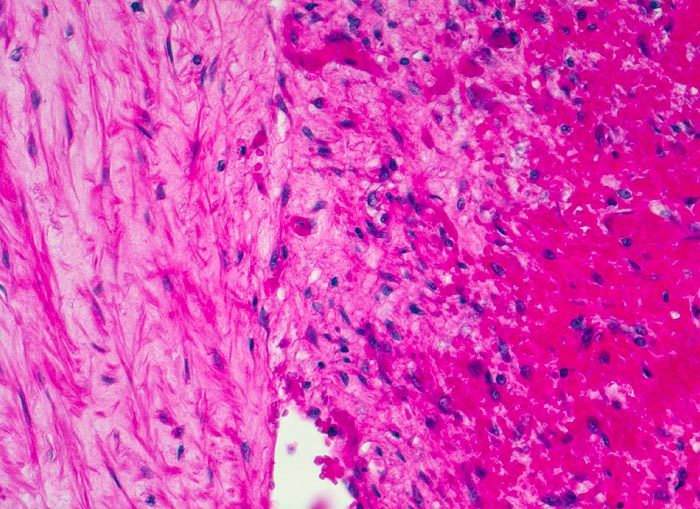

Venenthrombose in Organisation

Links im Bild die Intima der Vene. Rechts im Bild organisierter Thrombusanteil bestehend aus fibroblastenreichem Granulationsgewebe.

Todesursache: Multiple ältere periphere und frische parazentrale Lungenembolien.

Metastasierendes Tumorleiden. Der Patient wird tot im Bett aufgefunden.